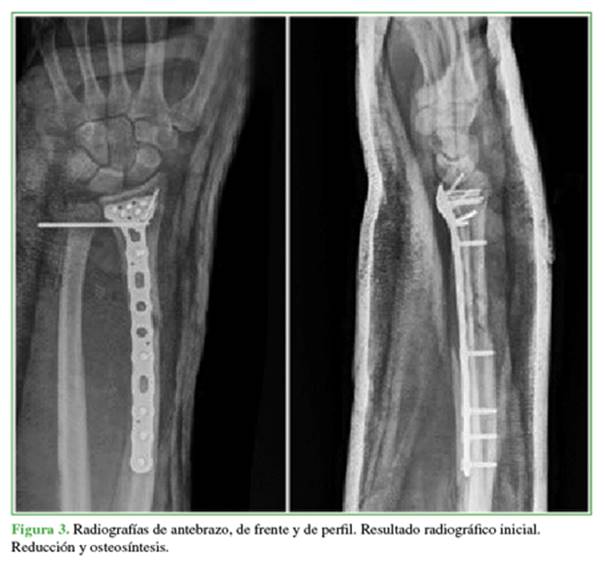

Hombre de 39 años de edad, que ingresó en el Servicio de Urgencias tras sufrir politraumatismos por un accidente de tránsito en motocicleta. Se diagnosticó una luxo-fractura expuesta de Galeazzi en el antebrazo derecho, Gustilo II (fractura diafisaria conminuta de radio y luxación radiocubital distal irreductible) (Figuras 1 y 2), por lo que se le indicaron antibióticos y cirugía de urgencia según el protocolo para fracturas expuestas. A los siete días, se procedió a la reducción abierta y fijación interna definitivas del radio derecho más la estabilización de la articulación radiocubital distal, con un buen resultado clínico-radiológico inicial (Figura 3).